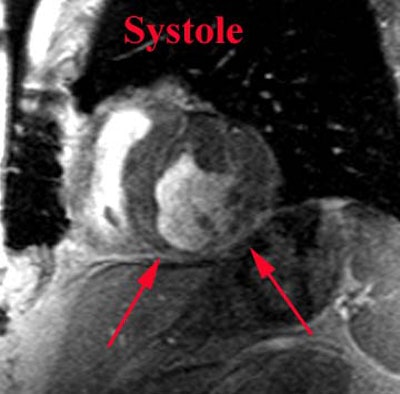

MRI: On MRI, acutely infarcted myocardium demonstrates increased signal intensity on T2 images.

.Prior MI: Below are two short axis views (diastole and systole) from a cine-GRE sequence of a patient with an inferior MI. The examination demonstrates thinning and lack of motion in the inferior wall consistent with an area of infarction. Case from Dr. Scott Flamm. |